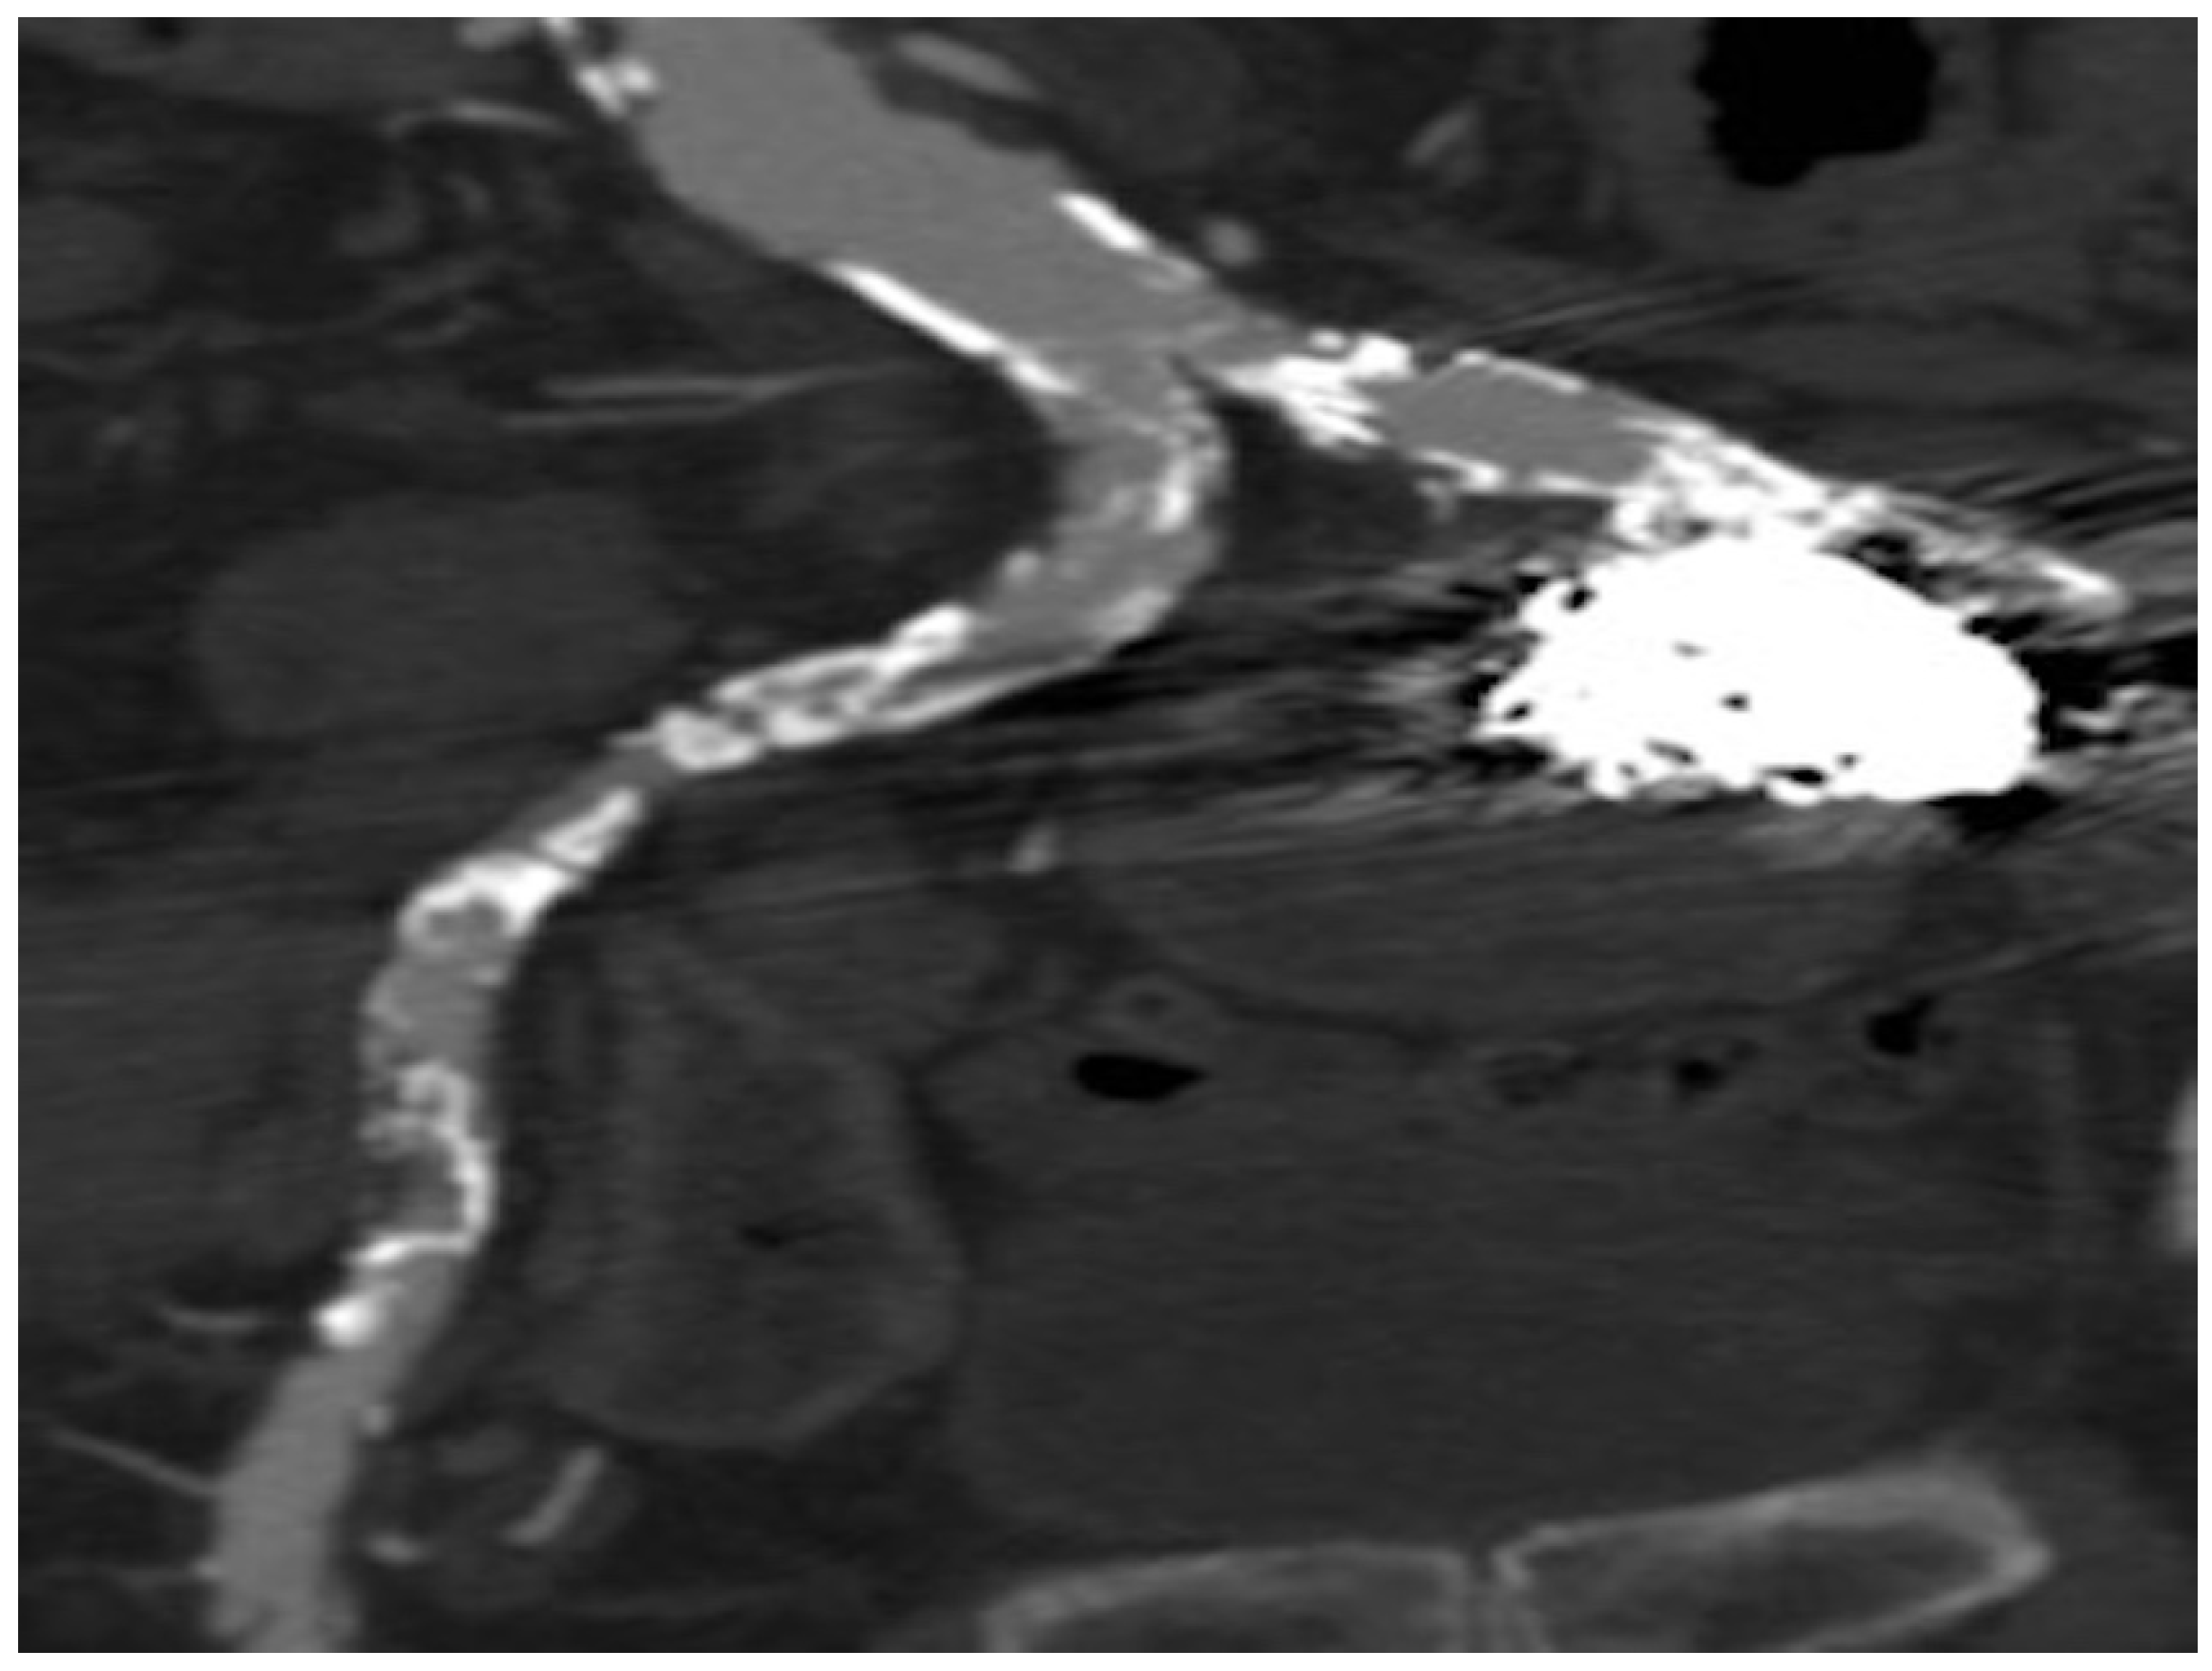

2. Case Presentation